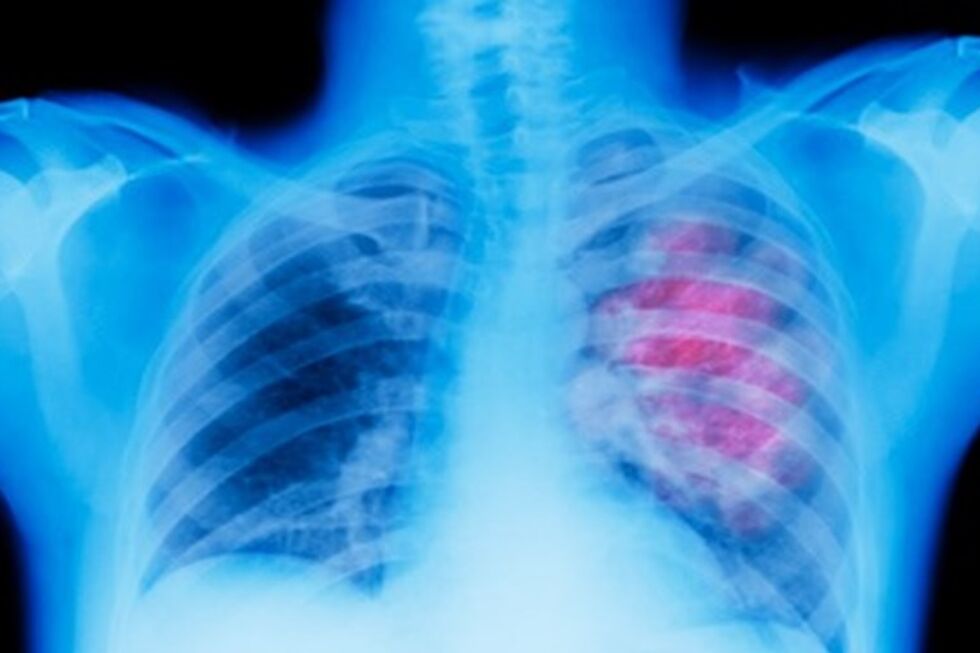

A incidência de cancro em Portugal deve aumentar 20% até 2040, com o país a apresentar as taxas mais elevadas de doença oncológica em crianças na União Europeia, alerta um estudo esta segunda-feira divulgado.

Os dados constam do perfil do cancro em Portugal apresentado pela Organização para a Cooperação e Desenvolvimento Económico (OCDE) e pela Comissão Europeia (CE) e que refere que a doença oncológica é a segunda principal causa de morte no país, com a taxa de mortalidade a diminuir a um ritmo mais lento do que a média da União.

As estimativas apresentadas no estudo apontam para um aumento dos novos casos de cancro em todos os países da União Europeia (UE) entre 2022 e 2040, mas com Portugal a registar um crescimento mais significativo.

Em Portugal, prevê-se que os novos casos de cancro aumentem 12% até 2030 e 20% até 2040, acima das médias da UE de 9% até 2030 e de 18% até 2040.

A OCDE e a CE referem ainda que, em 2022, terão sido diagnosticados cancros a 245 crianças e adolescentes até aos 15 anos, o que representa a taxa de incidência mais elevada entre os países da UE e da Islândia de Noruega, ficando acima da média da UE de 14 casos por 100.000 crianças.

À semelhança do que acontece na UE, em Portugal a taxa de incidência dos rapazes é ligeiramente superior à das raparigas e ambas essas taxas são aproximadamente 30% superiores à média da UE.

O estudo agora divulgado avança ainda que, em 2021, Portugal regista uma das maiores desigualdades entre homens e mulheres em termos de mortalidade por cancro.

Os homens (318 por 100.000) registam uma taxa de mortalidade por cancro que é praticamente duas vezes a das mulheres (161 por 100.000), o que se explica, em parte, com as três localizações de cancro mais mortais - pulmão, cólon e reto e estômago - e com a maior prevalência de fatores de risco comportamentais.

Entre 2011 e 2021, a mortalidade por cancro em Portugal diminuiu 8%, uma redução que foi inferior aos 12% registados na UE, indica também o perfil da OCDE e da CE, que salienta que as melhorias a nível da mortalidade ficaram aquém das de outros países, em especial entre as pessoas com menos de 65 anos.

Nesse período, Portugal conseguiu, porém, reduzir as taxas de mortalidade de alguns dos tipos de cancro mais frequentes - como o da bexiga (-34 %), do colo do útero (-26 %), colorretal (-22 %) e da próstata (-22 %) - mais rapidamente do que a média da UE.

Já as taxas de mortalidade por cancro do pulmão diminuíram 3% entre os homens, mas aumentaram quase 23% entre as mulheres, refletindo a evolução dos padrões dos fatores de risco comportamentais, refere ainda o perfil da doença no país.